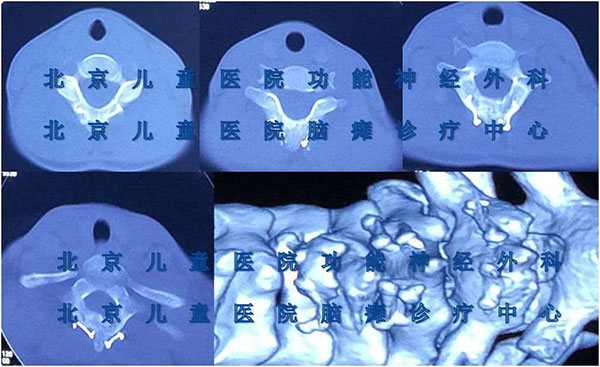

小儿痉挛性脑瘫,指在患儿大脑未发育成熟时期,由于各种原因造成了大脑的非进行性损伤、从而引发后期的运动和姿势紊乱;同时可伴有智力低下、惊厥、行为异常或感知觉障碍等等。目前,我国的脑瘫患者达600万例,并且每年新增脑瘫患者数量达到3~4万例;大约70%的脑瘫患儿属痉挛性脑瘫,按比例计算可达400余万例。 小儿痉挛性脑瘫可由产前、产时和产后各种原因引起。大多数脑瘫原因发生于产中。产前:1脑部先天性缺陷,常由于母亲在妊娠早期、怀孕头3个月时患风疹或其他病毒性感染所致。2胎儿产前期缺氧,主要源于胎盘破裂、胎盘梗死、母亲的肺炎或心脏疾病。3由母亲方面的不良因素而引发,如母亲患糖尿病、甲状腺功能异常、饮酒和服用药物等同样是引起脑瘫的产前原因。产时:产时最常见的原因为早产。若诞生时体重低于2kg,脑瘫发生的机会较多。其他通常是由于不正确应用产钳、难产或产程延长而产生分娩时创伤或缺氧所致。据统计,低出生体重儿和窒息儿易患痉挛性脑瘫。产后:常见的原因是脑炎、脑膜炎、创伤、血管意外和缺氧。小儿痉挛性脑瘫损伤主要在锥体系,造成四肢肌张力增高。上肢表现为腕关节掌屈,手握拳,拇指内收,手指关节屈曲,前臂旋前,肘关节屈曲,肩关节内收。下肢表现为尖足,足内、外翻,膝关节屈曲或过伸,髋关节屈曲、内收、内旋,大腿内收,常在行走时足尖着地,呈剪刀步态。患儿视觉功能发育不足,或者斜视、弱视,发音不清,流涎等。另外还可有不同程度的智力落后、胆小、畏缩、内向性格等。治疗上采取选择性脊神经后根切断改善高肌张力状态,然后进行系统康复治疗指导,以获取最好的疗效。选择性脊神经后根切断术是目前公认的、持久性缓解脑瘫患儿高肌张力状态的优选方法,疗效已较为明确。北京儿童医院脑瘫诊疗中心在国内率先使用超声骨刀切除椎板、然后再复位;超声骨刀形成骨缝的很小、椎板破坏较小,椎板复位后利于骨性融合形成(如图所见),减少了术后并发症以及功能受损。同时,进一步开展颈段选择性脊神经后根切断+椎板复位术,治疗上肢痉挛性脑瘫,也取得了满意的疗效。